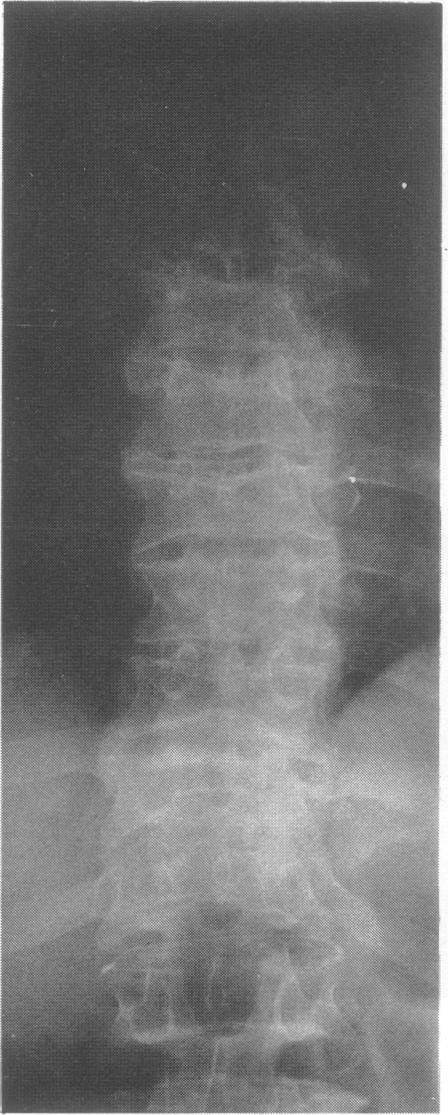

This survey reviews the diagnosis (predominantly radiological) of 32 cases of pseudoachondroplasia from 26 kindreds and illustrates the natural history and varying appearance of the disordered bone growth from infancy to adult life. In addition, an attempt has been made to detect phenotypic differences between autosomal dominant and recessive types (excluding isolated cases), analysing 10 kindreds of dominant inheritance (three in the current survey, seven from published reports) and six of recessive inheritance (three in the current survey, three from published reports). There appears to be no clinical or radiographical feature which clearly distinguishes them, but, using height as a criterion of severity, among those with autosomal recessive inheritance there was a disproportionate number of the most severely affected cases and there also appears to be very little intrafamilial variation. It is possible that pseudoachondroplasia can be subdivided into autosomal dominant mild and severe and autosomal recessive mild and severe, but full delineation must await elucidation of the basic defect at biochemical and molecular levels.

本调查回顾了来自26个家族的32例假软骨发育不全病例的诊断(主要是放射学诊断),并阐述了该疾病从婴儿期到成年期骨骼生长紊乱的自然病史及不同表现。此外,还尝试检测常染色体显性和隐性类型(不包括散发病例)之间的表型差异,分析了10个显性遗传家族(本次调查中有3个,已发表报告中有7个)和6个隐性遗传家族(本次调查中有3个,已发表报告中有3个)。似乎没有能明确区分它们的临床或影像学特征,但是,以身高作为严重程度的标准,在常染色体隐性遗传患者中,受影响最严重的病例比例过高,而且家族内差异似乎也很小。假软骨发育不全有可能可细分为常染色体显性轻度和重度以及常染色体隐性轻度和重度,但要进行全面分类,必须等待在生化和分子水平上阐明其基本缺陷。